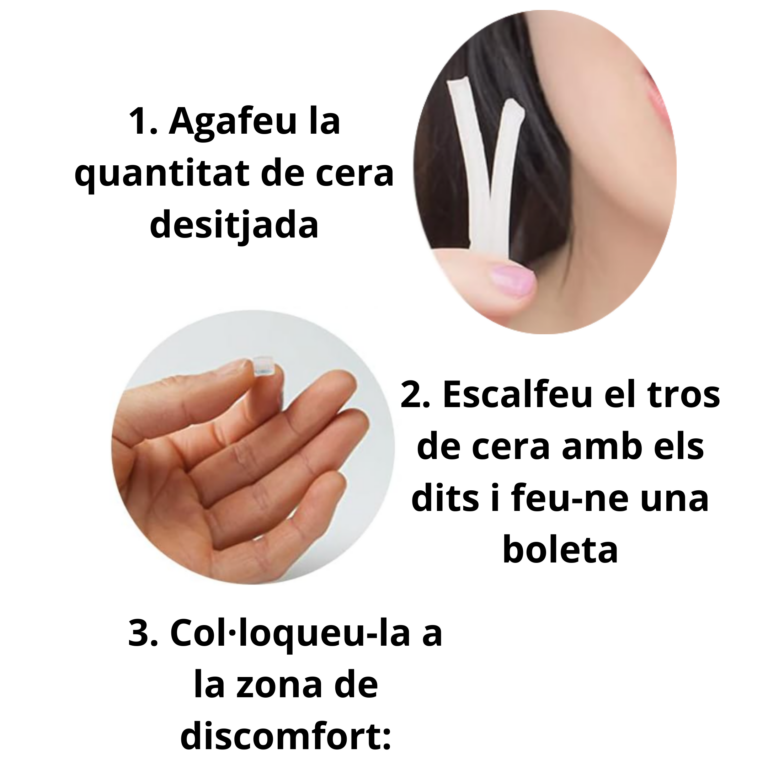

1. Llagues a llavi o llengua

Després de la col·locació de l’aparell, és habitual que s’hagi d’acabar d’assentar el metall amb la masticació i els teixits orals s’han d’acostumar a la nova presència de l’aparell.

Si la llaga està ocasionada per la fèrula, podeu tallar la zona que l’ha provocada

Si ha aparegut alguna llaga, realitzeu els passos següents 2 coses:

– Apliqueu Gel de clorhexidina la llaga, després de cada raspallat i a demanda entre raspallats si cal.*

– Apliqueu a sobre el metall que molesta una boleta de cera ortodòntica –> Amb dos dits agafeu un trocet, feu-ne una boleta i l’enganxeu-la sobre la dent i/o el metall que molesta.*

– Si la llaga està ocasionada per la fèrula, enlloc de posar la cera, heu de tallar la zona que l’ha provocada amb tisores de paper: